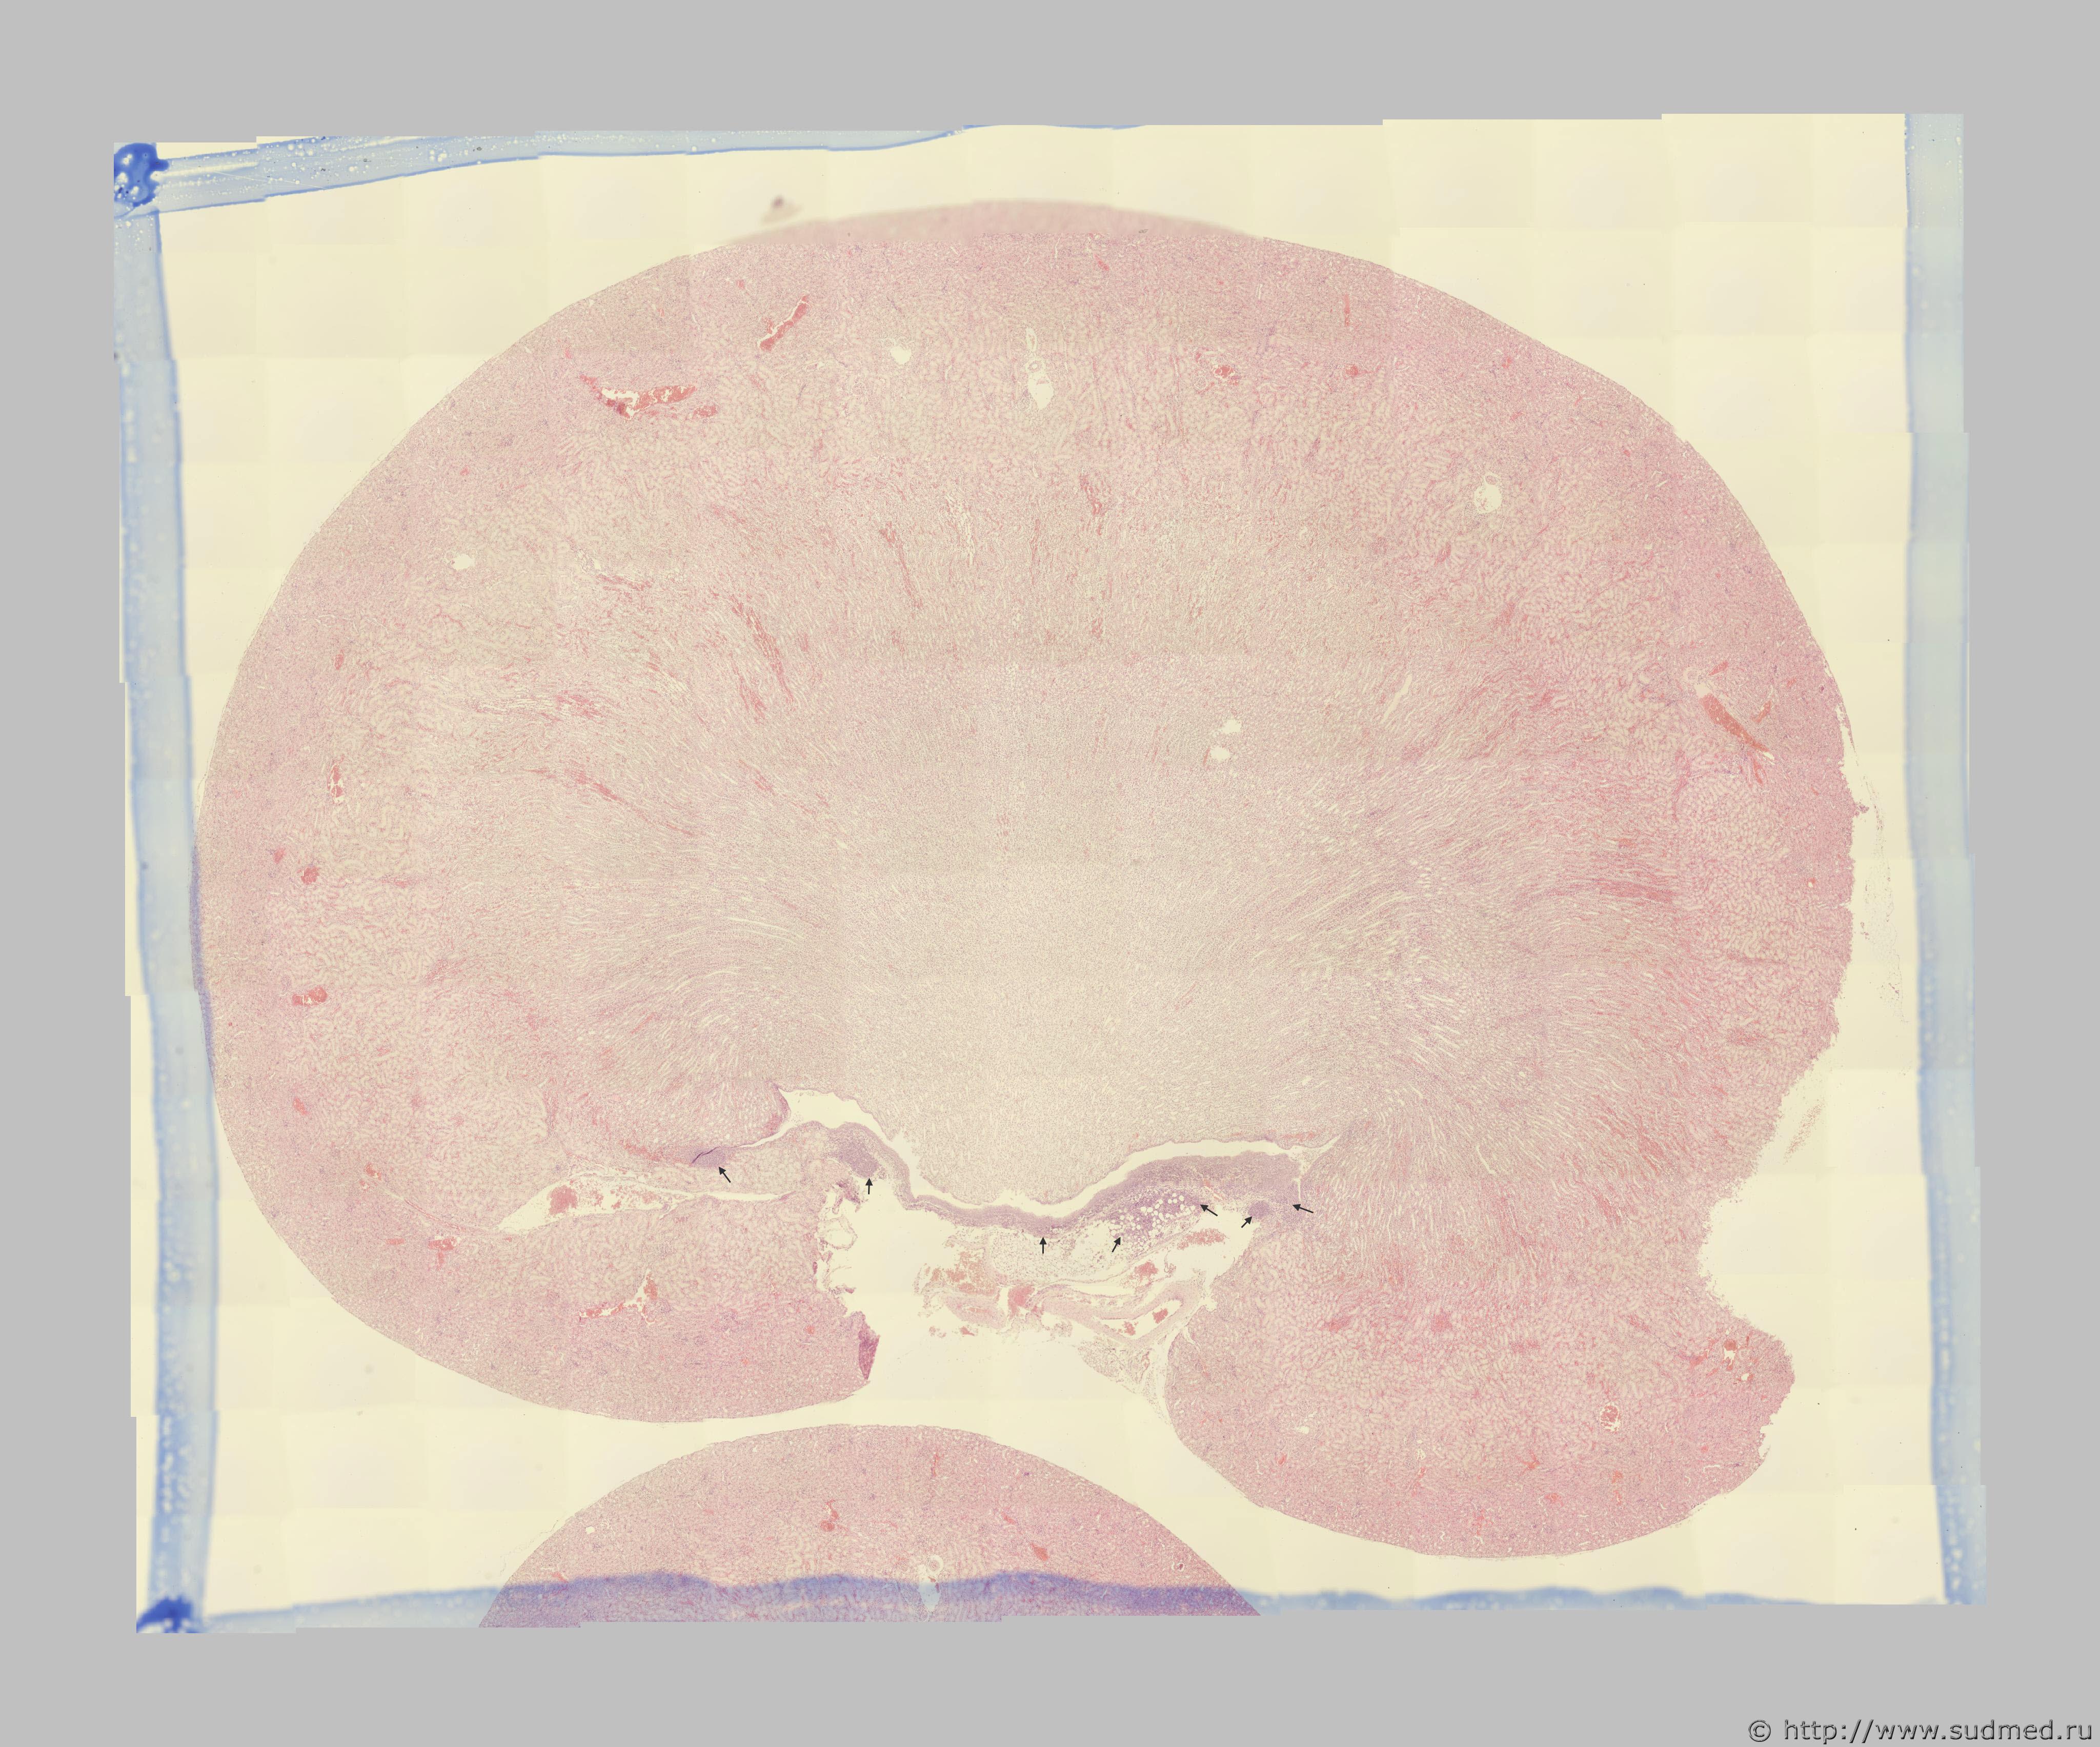

Имея в собственной практике просмотр несколько тысяч гистопрепаратов почек, такое наблюдаю впервые. В одной из почек отмечено:

выраженная инфильтрация прилежащей к наружной поверхности почечной лоханки соединительной и адипозной ткани мононуклеарами с преобладанием лимфоцитов без признаков пролиферативной активности со стороны последних;

формирование в указанной области единичных лимфоузлов;

очаговая инфильтрация эпителия почечной лоханки мононуклеарами.

Это аутоиммунный процесс или что то другое?

На первой фотографии стрелками указаны области инфильтрации, увеличение остальных фотографий х10, х20, х40

Возможно, это начальный этап развития указанного Вами процесса (хронический пиелонефрит), но со стороны почечной лоханки изменений нет, как верно заметила Жаклин, гиперплазия стенки лоханки тоже не наблюдается. В отмеченных стрелкой областях наблюдается масса лимфоцитов, среди которых встречаются единичные макрофаги. Лимфоциты атакуют лоханку снаружи, со стороны прилежащей соединительной ткани, т.е. воспалительный процесс развивается снаружи, а не изнутри.